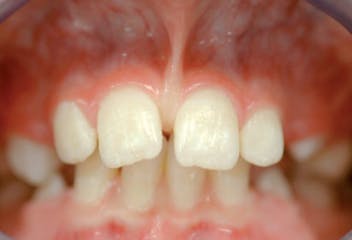

La rimozione chirurgica del frenulo labiale è una terapia che viene presa in considerazione quando si riscontra che questi possano essere associati a difficoltà di fonazione, all'instaurarsi di condizioni parodontali patologiche come le recessioni gengivali o alla promozione di diastemi interincisali (spazio tra i denti incisivi).

Il fattore dirimente sta nel saper cogliere il momento adeguato di sviluppo ed eruzione dentaria in cui eseguire la rimozione del frenulo.